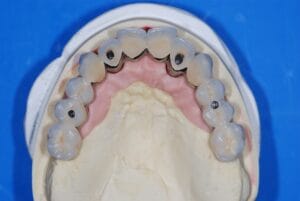

Using a 3D navigation system, our dentists position implants digitally at the perfect angle and depth. This plan is then transferred into a customised surgical guide and if needed temporary teeth, which can be placed directly onto the newly placed implants.

Step 4 – Surgery day